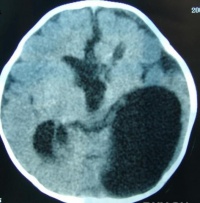

1.CT表现:

(1)呈均匀或不均匀的低密度改变,CT值 0-15HU,边缘清楚。

(2)有两种形态:

①扁平型:形态不规则,肿瘤沿蛛网下腔蔓延,“见缝就钻”为其特点。

②团块型:多位于硬膜外,呈球形,为混杂密度。

(3)肿瘤可有钙化,但不常见,多位于囊壁上,亦可在囊内。

(4)脑桥小脑角池、环池四叠体池的肿瘤可致脑干受压、变形;

(5)增强扫描时病灶不强化,偶见边缘轻度弧形增强。

3、CT和MRI扫描 CT见瘤体为边界清楚、形态不规则、呈均匀的低密度影,少数为混杂密度。增强后无强化。MRI在T1加权上表现为略高于脑脊液的低信号影,T2加权上为略低于脑脊液的高信号。注射增强剂后囊肿无强化为其特征。